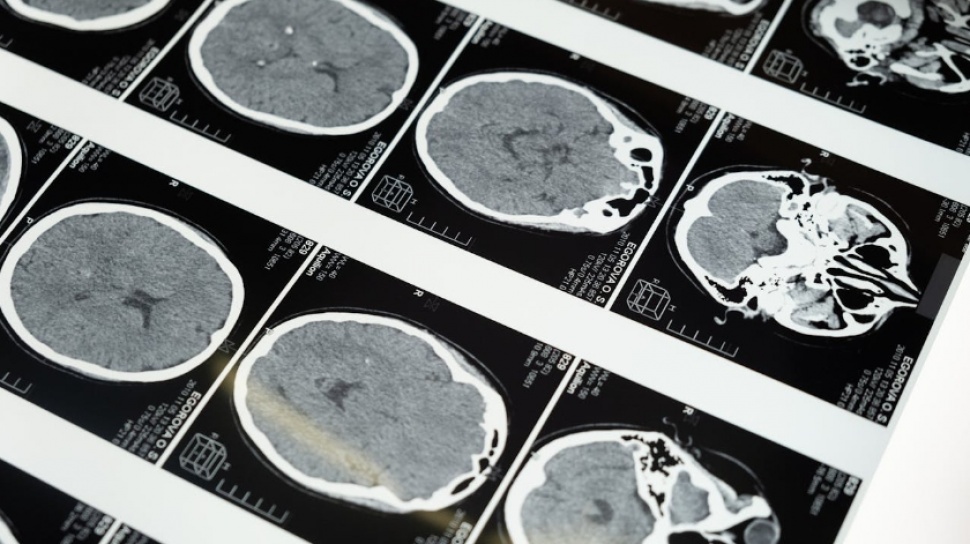

Studi terbaru mengungkap bahwa perkembangan otak manusia tidak berjalan secara linier melainkan melalui lima fase utama yang dipisahkan oleh titik balik penting. Temuan ini didasarkan pada analisis hampir 4.000 pemindaian otak dari individu berusia mulai dari bayi baru lahir hingga lansia berusia 90 tahun.

Penelitian yang dipublikasikan dalam jurnal Nature Communications ini menunjukkan bahwa titik-titik perubahan signifikan terjadi pada usia 9, 32, 66, dan 83 tahun. Selama periode tersebut, struktur dan fungsi otak mengalami transformasi yang berdampak besar pada perkembangan kognitif dan kondisi kesehatan mental seseorang.